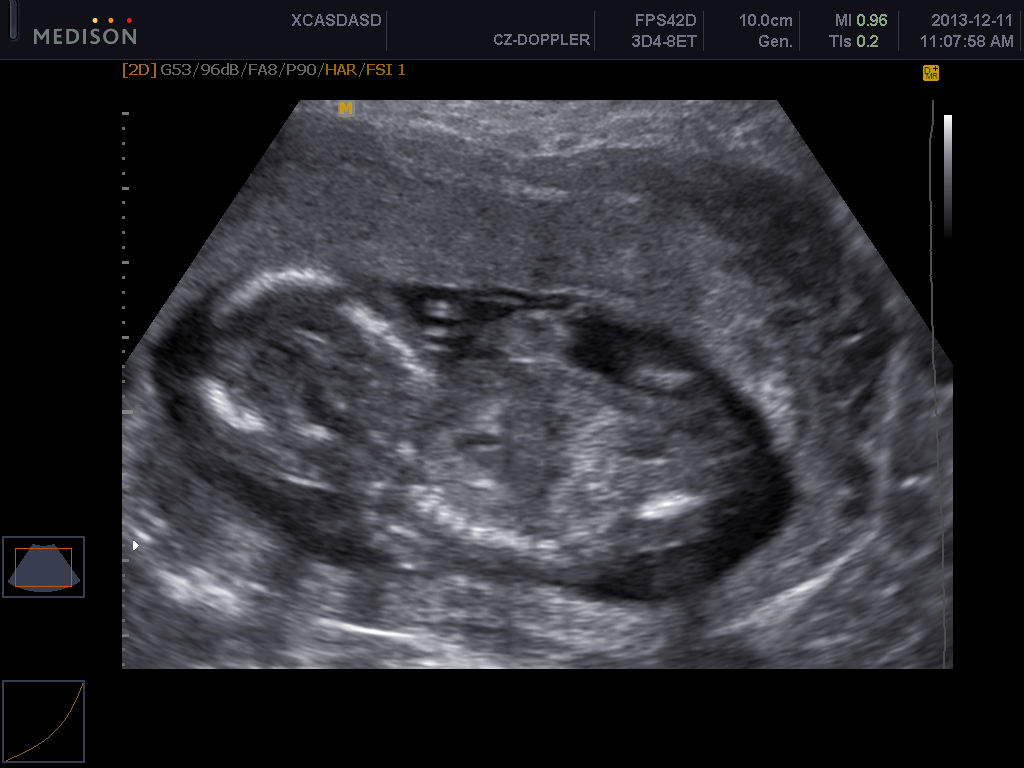

A taky se musím holky pochlubit nejen chlapečkem,ale taky mám první fotečku..jupííí..a k tomu rovnou nahrané video mimíska jak se v bříšku kroutí a platila jsem jen symbolických 200Kč za 3 fotky na papíru a 5 fotek + 2 videa na CD.

Zkusím tady to video dát,ale nevím jestli půjde spustit...tak raději vložím i fotečku

Pety 1-moc krásné video a je krásně vidět že to bude chlapeček,moc gratuluji!!!!

Pety1 ještě kolikátý týden jsi,na tom videu?děkuji moc